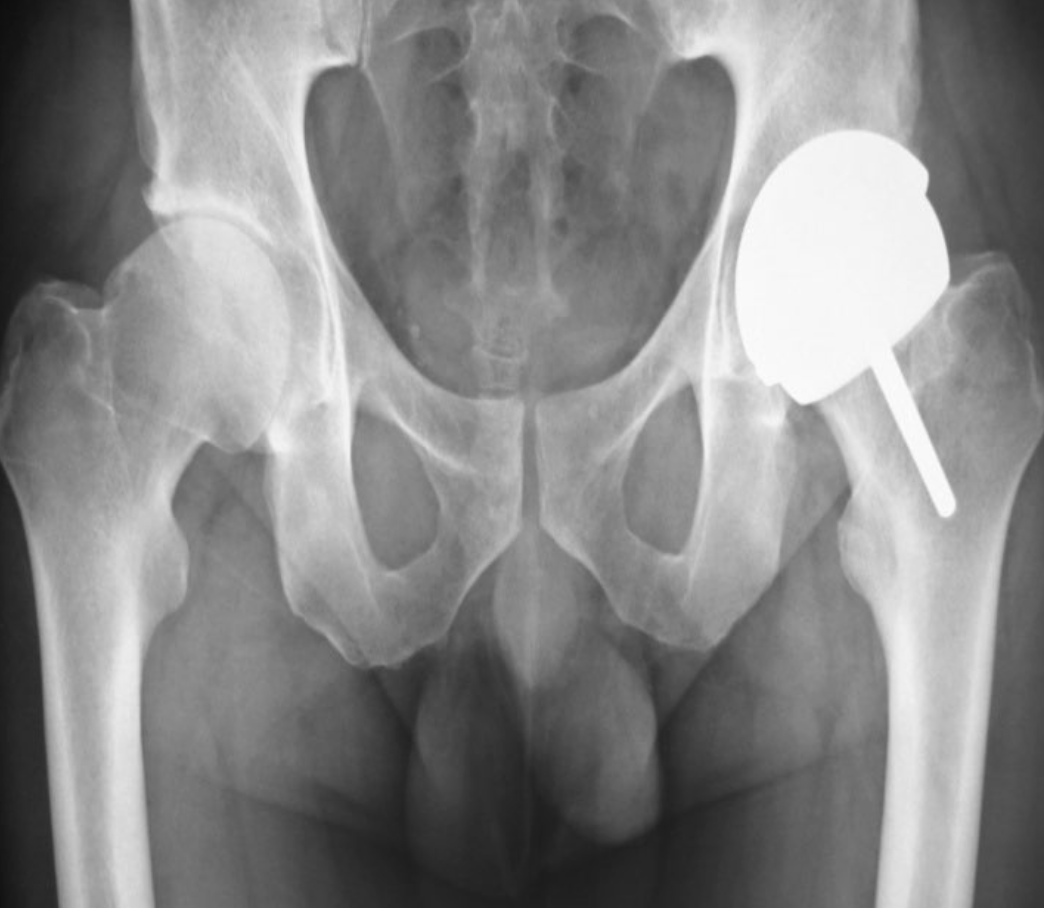

Artroplastia Total da Anca

Consoante as indicações, o tipo de prótese da anca é variado

. Prótese parcial Bipolar

. Prótese Total da Anca, podendo os seu componentes serem cimentados ou integrados.

A artroplastia total da anca pode ser cimentada, não cimentada ou híbrida (combinação de componentes cimentados e não cimentados). Nas próteses cimentadas, o cimento (Polimetilmetacrilato – PMMA) fixa o implante ao osso. Nas próteses não cimentadas a superfície das próteses é texturada ou apresenta um revestimento que permite que o osso se fixe aos implantes.